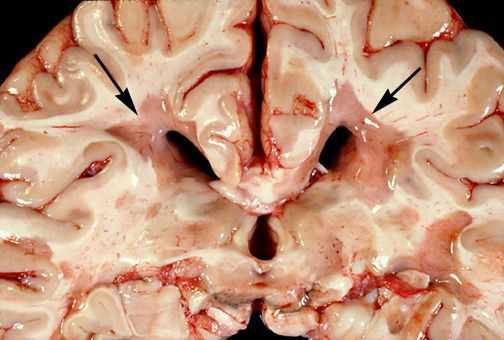

Для того, чтобы понять механизм развития РС, необходимо ознакомиться с патологической анатомией данного заболевания.

При микроскопическом исследовании обнаруживаются заметные и достаточно характерные изменения, выявляемые с наибольшим постоянством в спинном мозгу, мозговом стволе и полушариях головного мозга. Видны множественные бляшки различной величины (от точечных до весьма массивных, которые, к примеру, занимают весь поперечник спинного мозга), рассеянные преимущественно в белом веществе. Такая множественность и разбросанность очаговых изменений и определяет название болезни.

![Очаговые изменения в белом веществе мозга]()

Отдельные бляшки имеют округлую форму, они нередко сливаются и создают изменения сложных очертаний. Цвет бляшек на разрезе розовато-серый (недавно образовавшиеся очаги) или серый, желтоватый (старые очаги).

![Образовавшиеся бляшки]()

При разрезе бляшки определяется их большая плотность по сравлению с нормальной мозговой тканью. Эти уплотнения, склерозирование бляшек дало возможность охарактеризовать заболевание как склероз.

При микроскопии на первый план выступают изменения миелиновых волокон. В области очага, бляшки, в белом веществе наблюдаются в той или иной степени распад миелиновой оболочки, покрывающей нервные волокна центральных проводников, причём осевой цилиндр нередко остаётся неповреждённым.